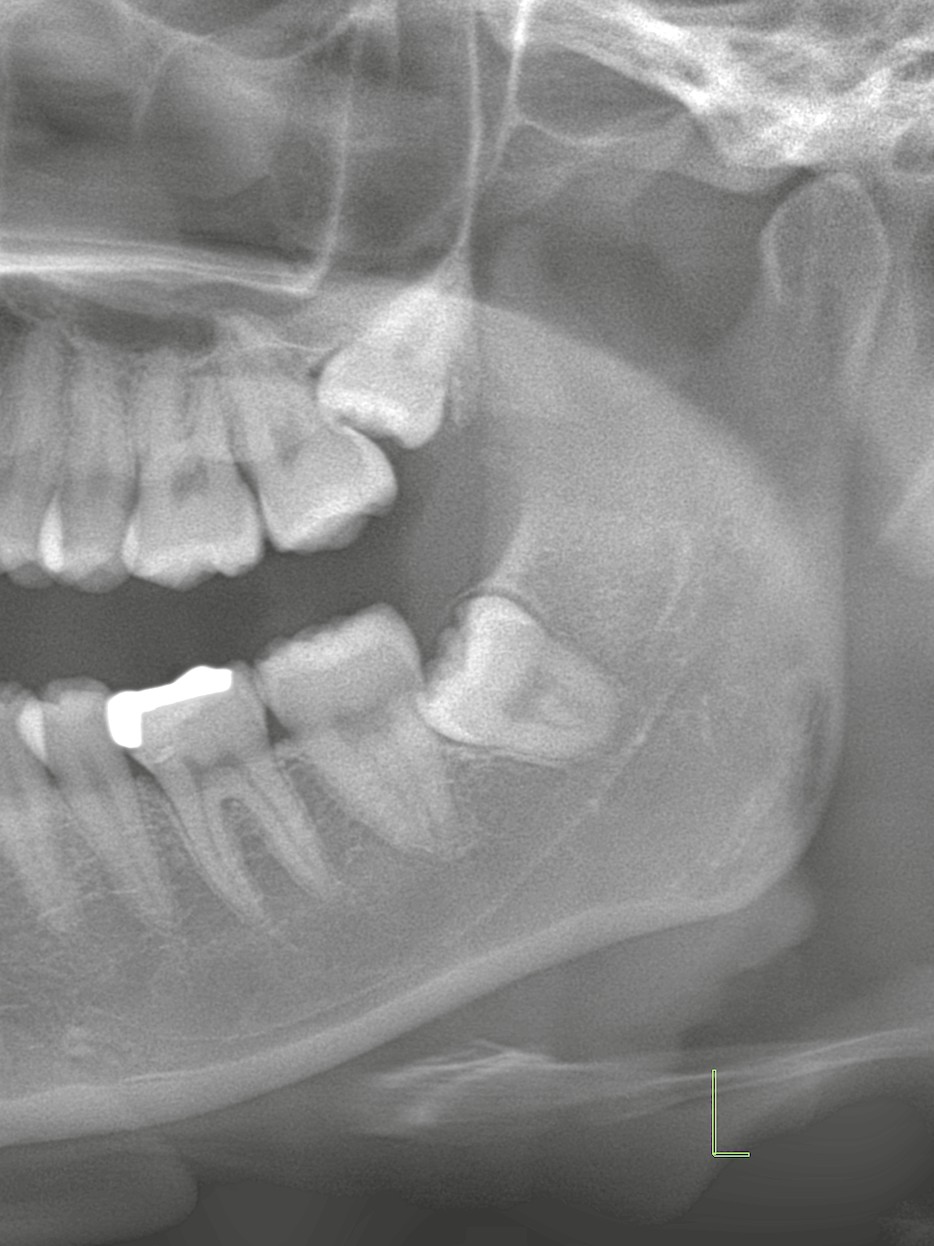

レントゲン所見

レントゲン検査で判明したのは、左上の親知らずが水平に萌出し、左上第二大臼歯に顕著に接触している状態。

このまま放置すると、第二大臼歯の歯根吸収や虫歯のリスクが高まります。

さらに下顎にも埋伏親知らずがあり、今後同様のトラブルにつながる可能性があるため、抜歯が妥当と判断しました。